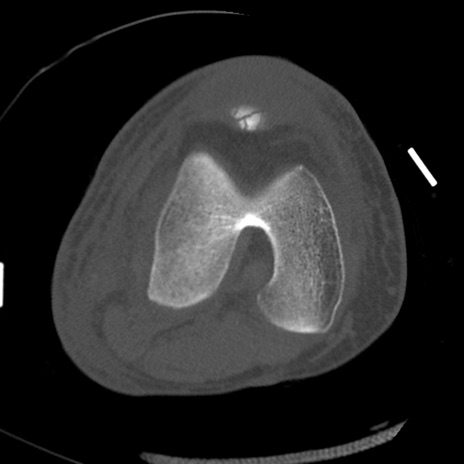

症例28 右膝関節CT(横断像)

右膝関節CT